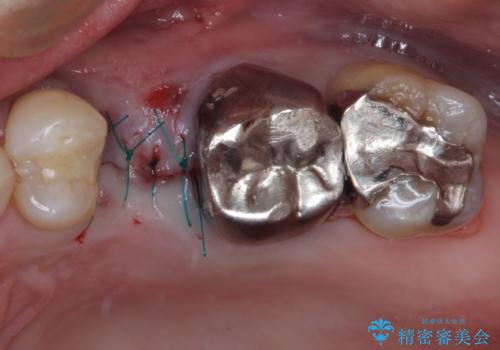

- 頻繁に銀歯が外れてしまうとのことで来院された患者様です。

歯肉の中、深いところまでむし歯が進行しており、歯根を部分矯正で引っ張り出してから補綴治療を行うか、抜歯してインプラント補綴治療を行うか選択することになりました。

海外での勤務があり、部分矯正は困難とのことで、インプラントによる補綴治療を行うこととしました。

より審美的で、より機能的に優れた治療をご希望とのことであったので、ジルコニアカスタムアバットメントを用いたインプラント治療を行うこととしました。

ジルコニアカスタムアバットメントは、歯肉ラインに金属が見えにくいというだけでなく、クラウンを装着する土台の形が天然歯と近い形態となるため、清掃性が高く歯肉が腫れにくいというメリットがあります。

インプラントは、骨との生着能が比較的高いとさせるSLAタイプを使用しました。